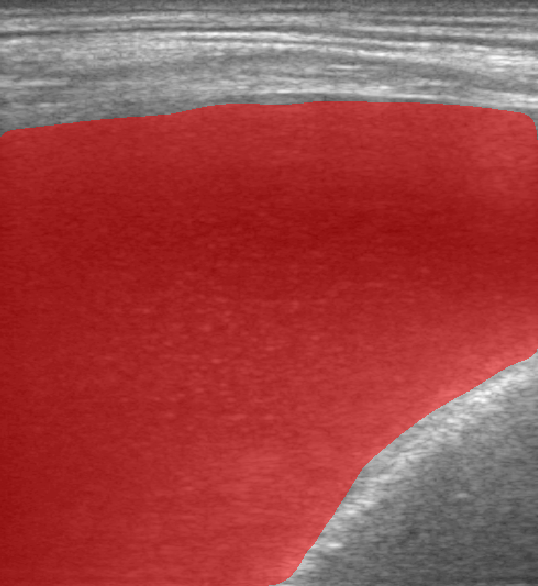

A total of 143 images were acquired from 59 patients. The images were obtained at the left and right PLAPS (PosteroLateral Alveolar and/or Pleural Syndrome) and subcostal views [4] with linear array and curved array (abdominal) ultrasound probes. The data were split according to the use of these probes into two datasets of 51 and 92 images, respectively for linear array and curved array. We denote these datasets as Dataset A (linear array) and Dataset B (curved array). All images were annotated at the time of acquisition to measure the extent of the effusion. These annotations consisted of small crosses at the top and bottom of the deepest area of effusion. See Figure 1 (left column) for example images.

Before being used for training and evaluating the models, each image was automatically cropped using a rectangular/cone mask to remove non-imaging content. Next, we applied an inpainting text algorithm using keras-ocr followed by template matching and edge detection algorithms from opencv to remove the annotations that were added to the images to measure the effusion. Examples of the outputs of this preprocessing are shown in Figure 1 (centre column).

All images in both datasets were manually segmented using the ITK-SNAP software [14] (www.itksnap.org) by a trained observer. Examples of ground truth segmentations are shown in Figure 1 (right column). These segmentations acted as ground truths for training and evaluating the proposed models. Additionally, a second trained observer performed independent segmentations of subsets of 10 random images each from the two datasets. These were used to compute an estimate of inter-observer variability in the manual segmentation process.

Rows 1-2: Dataset A. Rows 3-4: Dataset B.